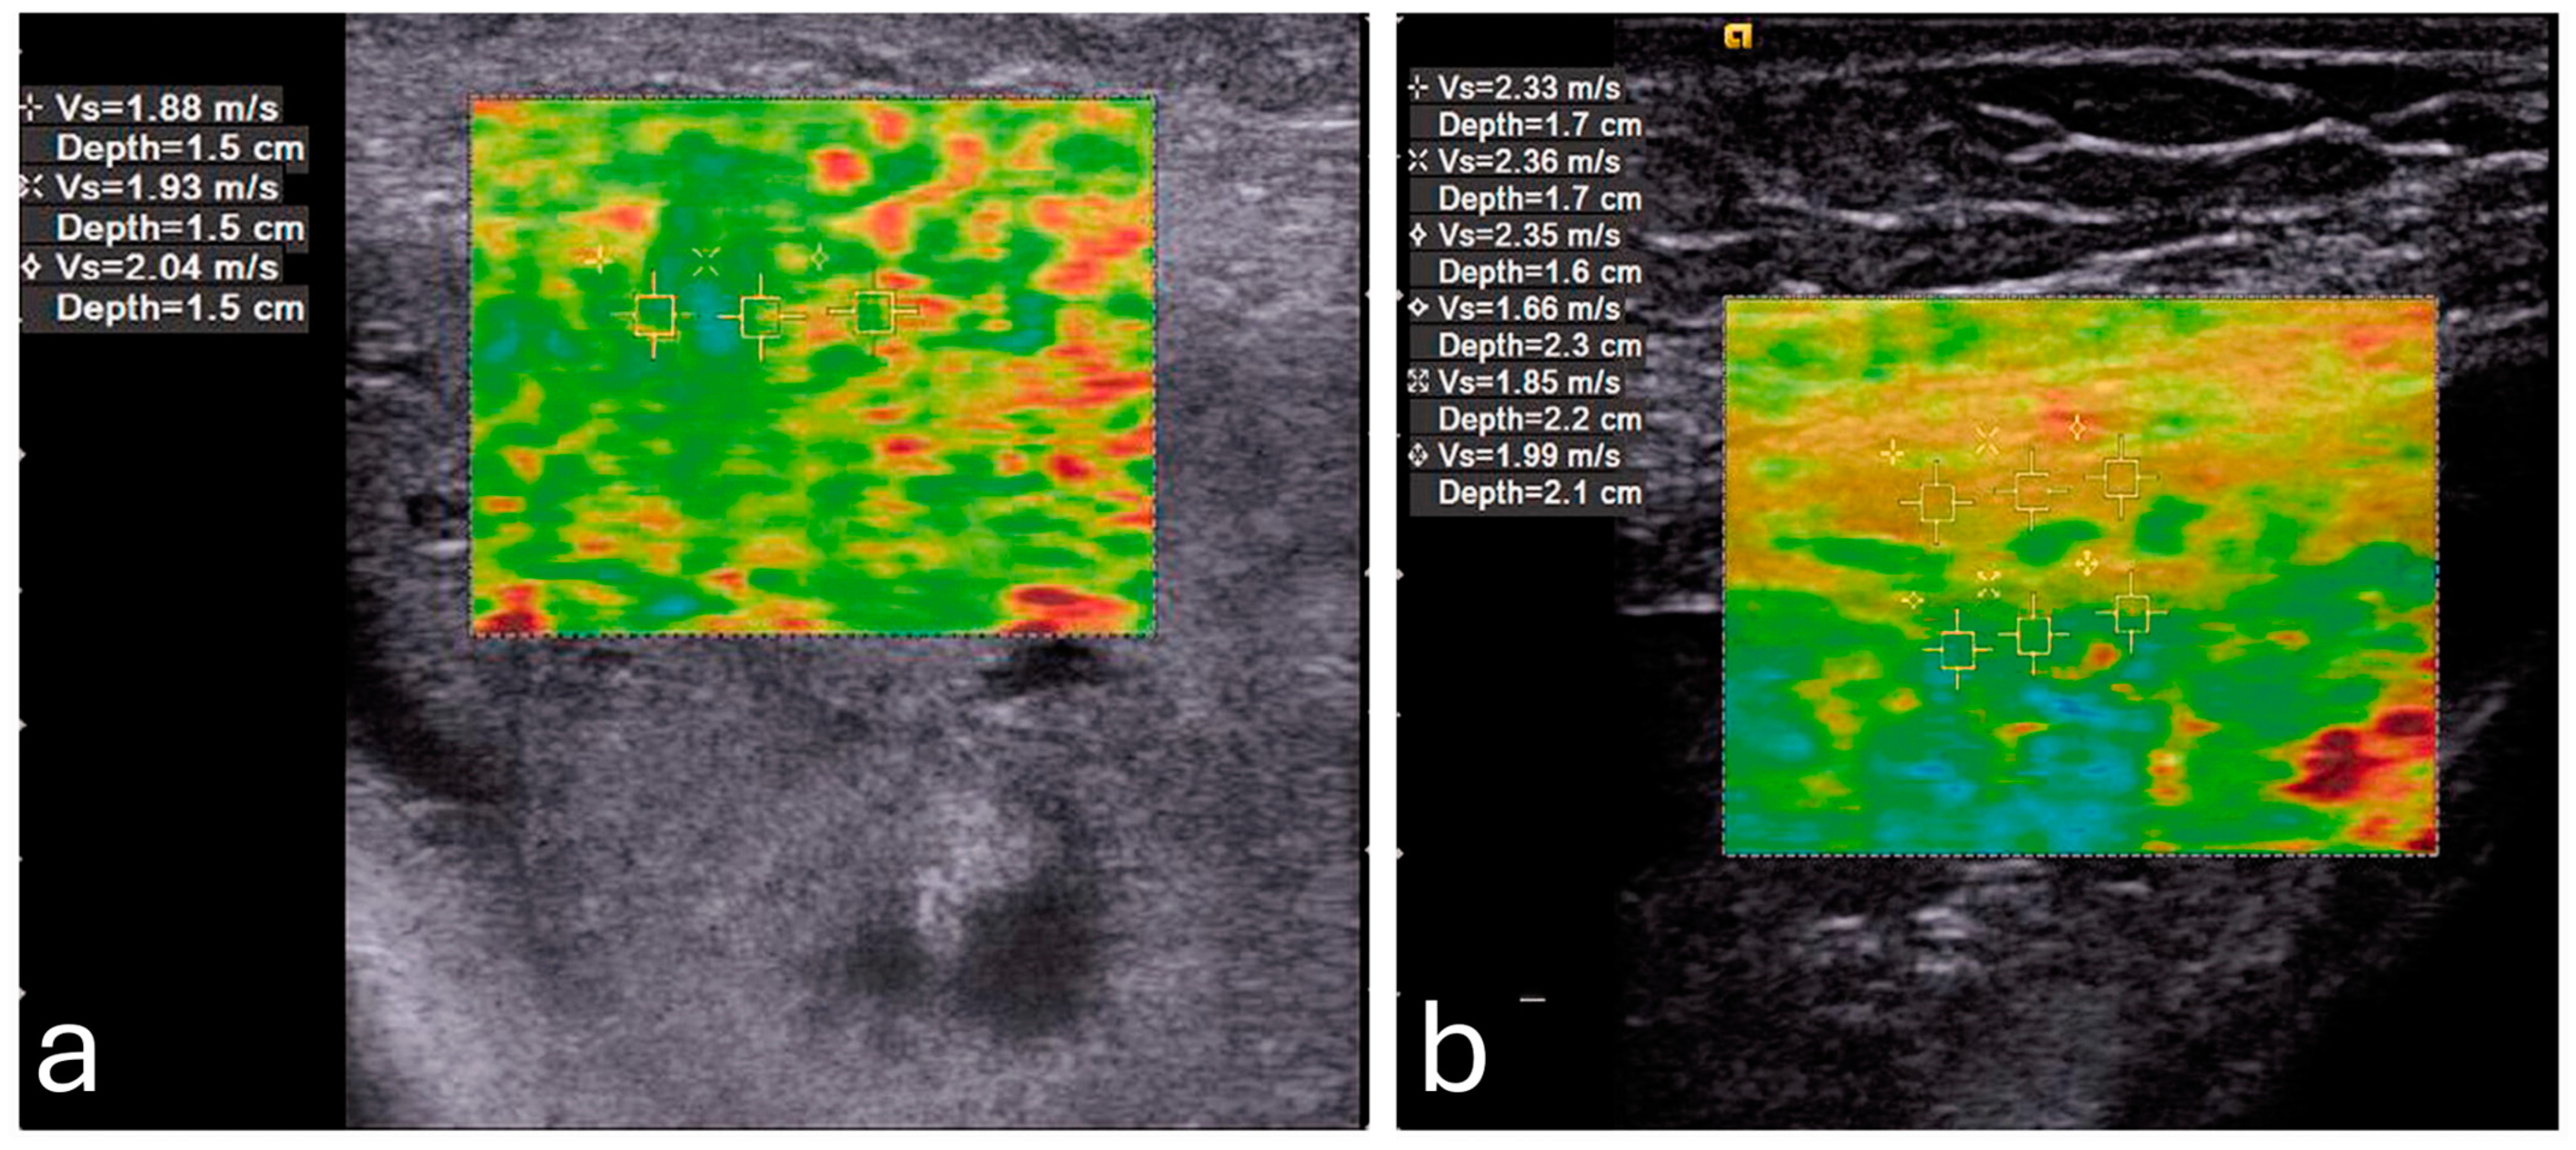

One of the primary factors influencing placental elasticity is the layered arrangement of the chorionic villi, which are densely populated with capillaries and responsible for mediating maternal–fetal nutrient transfer. As trophoblastic cells invade and remodel maternal spiral arteries early in pregnancy, the placental vascular network expands, allowing the tissue to maintain elasticity and accommodate increased blood flow. These vascular adaptations support fetal growth and contribute to the biomechanical softness measured by elastography []. In contrast, elastography detects increased stiffness in cases of placenta percreta, as illustrated in Figure 2 [].

Figure 2. A pregnant woman with placenta percreta showing (a) increased average shear wave velocity (1.95 m/s) in comparison to a pregnant woman with normal placenta showing (b) normal average shear wave velocity (1.83 m/s). Reproduced with permission from Sage. © 2024.

Emerging evidence highlights the potential role of sonoelastography in the evaluation of PAS. A study by Cim et al. used Virtual Touch Quantification (VTQ) techniques, a relatively older generation of elastography, to assess placental invasion anomalies []. They found significantly higher shear wave velocities (SWV) in cases with detected invasion compared to non-invasive cases across all regions of the placenta, with an average SWV of 2.862 ± 0.815 m/s in the invasion group versus 0.926 ± 0.484 m/s in the non-invasion group (p < 0.001) [].

Dokumaci and Uyanikoglu further supported these findings by demonstrating that SWE could differentiate placenta percreta cases from normal pregnancies []. In their case-controlled study, the mean SWV values of the maternal edge of the placenta were 1.95 ± 0.19 m/s for placenta percreta cases and 1.69 ± 0.23 m/s for controls, with a cutoff value of 1.92 m/s, achieving 80% specificity for detecting PAS [].